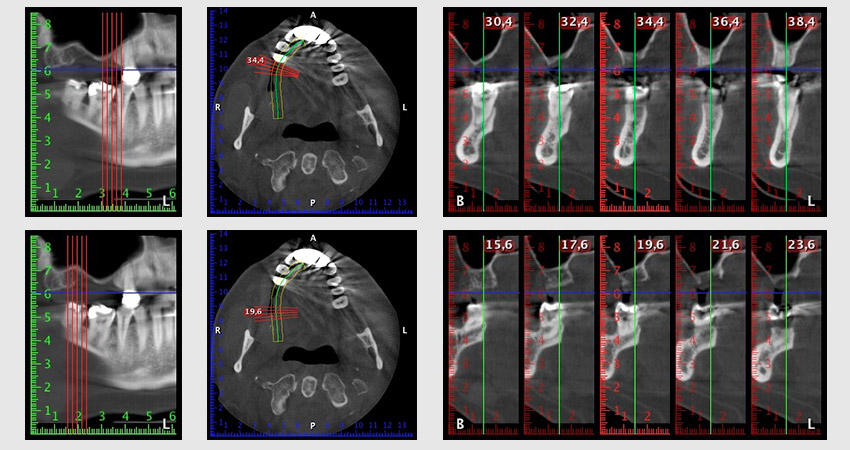

Al fine di pianificare e minimizzare i rischi, circa sei mesi dopo l'estrazione dei denti 16 e 14 viene effettuata una tomografia digitale volumetrica (DVT, Planmeca), la quale conferma chiaramente la mancata rigenerazione ossea nel volume desiderato (da fig. 2 a 7).

Da immagine 2 a 7: DVT con volume osseo orizzontale notevolmente ridotto.